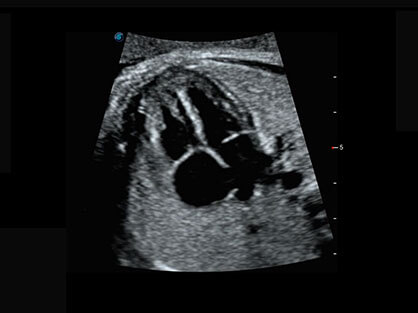

作为P系列家族成员之一,P40 Plus采用球速体育入口高端超声系统平台——极光,并以时尚秀丽、小巧灵动的外观设计绽放出灵动之韵、科技之美。高端平台的使用保证了P40 Plus优质的基础图像;完备的高级功能可满足您全身应用的基本需求;丰富的探头配置、多样的高级4D成像及分析软件为您日益增多的妇产应用需求提供丰富的诊疗方案。

结合球速体育入口超宽频带探头技术优势,能够更好地获得高分辨力与高穿透力的平衡,保证图像质量,为临床诊断保驾护航。

微米成像技术提升了对组织斑点噪声信号的抑制能力,并进一步强化边界信息,从而获得清晰图像。